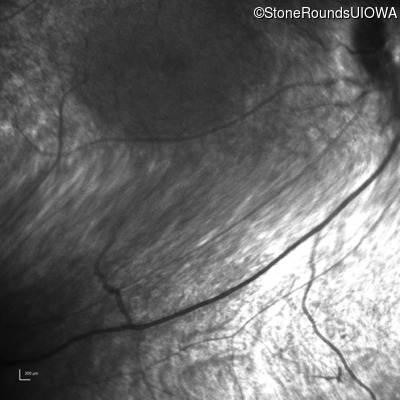

Infrared Fundus Photograph - Left - Light Perception

Exemplar